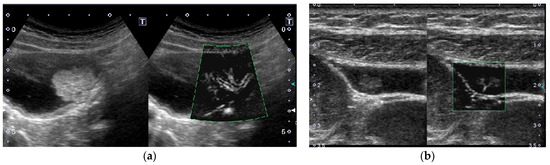

Figure 10. Vascular imaging using superb microvascular imaging (SMI). (a) Multiple flow signals spreading dendritically from the base into the lesion were delineated in a GBC. (b) A branched signal was detected in a cholesterol polyp.

Color Doppler imaging is used to detect vessels inside GPLs and GB wall, and evaluate its direction. Since the most recent highly-sensitive Doppler imaging can detect low-flow signals, minute vessels in GPLs can be evaluated without using contrast agents (Figure 10). In previous reports, color signal patterns have been roughly classified into absent, diffuse, dotted, linear, irregular, branched, tortuous, arborizing, and so on. Hirooka et al. [52] reported that color signal patterns of GBCs were diffuse or arborizing (sensitivity 90.5% and specificity 62.5%).

As for CEUS, Miwa et al. [13] proposed shape (regular or irregular) and thickness (dilated or thin) as parameters for classifying vessels: Vessels of GBC were irregular in 82% and dilated in 71%, whereas in cases of benign polyps, 95% had regular and 89% had thin vessels. Dilated vessels, characterized by caliber changes of approximately 1 mm in diameter on CEUS, were significantly correlated with malignant GPLs (p < 0.001) [13]. Kin et al. [53] reported that contrast-enhanced SMI provided a microvascular image with good quality compared with SMI, and tortuous microvessels and the presence of abrupt caliber change in microvessels showed a significant difference between benign and malignant GB lesions (p = 0.032, p < 0.001, respectively). However, irregularly shaped signal patterns and dilated blood vessels were detected even in non-neoplastic GPLs in a few cases [13,52,53]. Measurement of GB wall blood flow (GWBF) is another clue for differentiation. GBC showed a significantly rapid blood flow value compared with other GB abnormalities and healthy volunteers. When the cut-off level of GWBF velocity was set at 30 cm/s, GBC could be diagnosed with 100% sensitivity and 96% specificity [54].